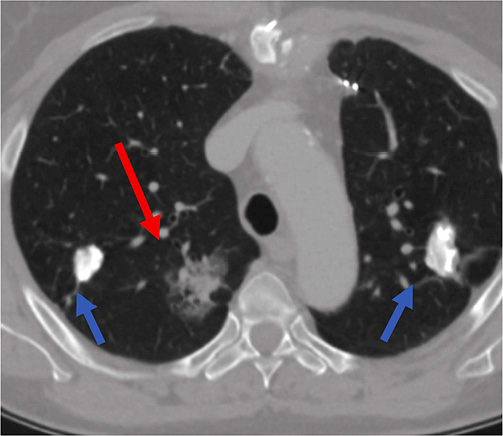

Figure 2. Biopsy of the right lung lesion. Coaxial needle punctured peripheral area of the lesion (blue arrow). Patient is in prone position during the biopsy.

Lung biopsy procedure was performed under local anesthesia in a prone position and the patient was instructed of shallow breathing. 17 gauge coaxial needle was inserted under CT guidance and proceeded up to the lung needle while lung biopsy was performed with 18 gauge needle with automated biopsy gun (Figure 2) sampling two biopsy specimen cores.